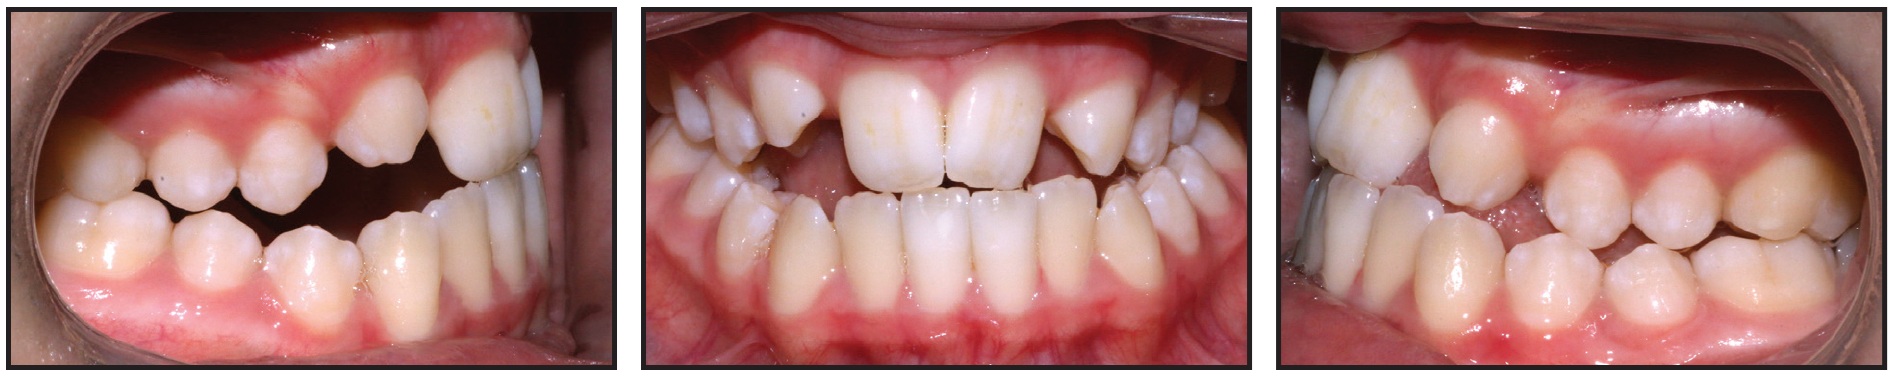

Unwanted Lower-Incisor Rotations from Premature Contacts

This patient presented with rotations from canine to canine in both arches (Fig. 5A). After 10 months of clear aligner therapy, the most severe rotation (the lower left lateral incisor) had been corrected, but a minor derotation of the lower right lateral incisor was still needed for ideal alignment (Fig. 5B). Even after an extra set of aligners, the rotation of the lower right lateral incisor was still unresolved (Fig. 5C).

Fig. 5 A. Patient with rotations from canine to canine in both arches before treatment. B. After 10 months of clear aligner therapy, minor rotation of lower right lateral incisor remaining. C. After extra set of aligners, rotation of lower right lateral incisor still unresolved.

Although premature contacts are easily ignored in an orthodontic practice, they can have serious effects on the tooth structure and support. Routine three-dimensional intraoral scans can easily show us where they are located. In this case, there was a strong contact between the upper right central incisor and lower right lateral incisor (Fig. 6). This contact should have been adjusted before more aligners were fabricated, but the premature contact with the distal marginal ridge of the upper right central incisor was clearly preventing derotation of the lower right lateral incisor (Fig. 7).

At this point, a selective occlusal adjustment was performed, and the rotations were entirely corrected with a few additional aligners.

It is not always possible to avoid premature anterior contacts due to the desired tooth positions or anatomy, the tooth-movement plan, or many other treatment-related factors. Nevertheless, occlusal contacts should be checked regularly in all cases. Every clinician should become familiar with the occlusal-adjustment techniques that will enable maximum intercuspation.

Inadequate Root Control of Lower Lateral Incisors

With the growing popularity of clear aligner therapy, it becomes more crucial to address the specific issues of root control. We often focus on the maxillary lateral incisors, due to their challenges in tracking. In extraction cases, we focus on root control of the canines and premolars, aiming for root parallelism. Unfortunately, we tend to overlook the mandibular lateral incisors. If the patient has a deep curve of Spee, the lower lateral incisors often exhibit a mesial angulation that we need to manage. In addition, when planning extraction treatment, we should remember that the incisor retraction can add a distal crown tip, which must be controlled with distal root angulation of the lower lateral incisors. Failure to achieve proper root angulation can lead to such undesirable outcomes as improper alignment, instability, and compromised occlusion.

Although the Invisalign system offers protocols for extraction cases and optimized attachments, the lower incisors lack root-control attachments, obliging us to customize the plan with conventional attachments. Regardless of your preferred clear aligner system, you should consider incorporating distal root movements and adding vertical attachments for the lower lateral incisors to facilitate distal root angulation.

In this case, a 21-year-old female presented with a Class I malocclusion, excessive overjet, deep overbite, severe crowding, and bimaxillary protrusion (Fig. 8).

Fig. 8 21-year-old female patient with Class I malocclusion, excessive overjet, deep overbite, severe crowding, and bimaxillary protrusion before treatment.

We planned four premolar extractions, maximum anchorage, leveling of the curve of Spee, and incisor retraction. In the initial treatment design, I made the mistake of not adding attachments to the lower lateral incisors (Fig. 9).